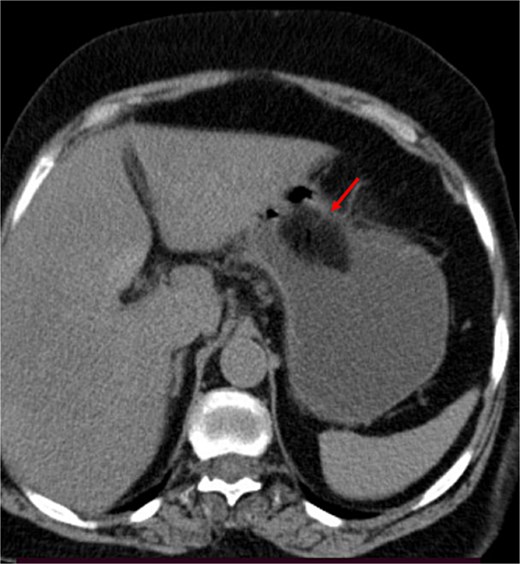

A contrast-enhanced CT of the abdomen was performed and revealed an intraluminal mass in the pylorus causing gastric dilatation (Fig. 1) and another intraluminal mass in the terminal ileum causing small bowel dilatation (Fig. 2). A nasogastric tube was inserted, and the patient was taken for exploratory laparotomy. There were significant gastric and small bowel dilatations; a gastrostomy and enterostomy were performed, and two foreign bodies were extracted (Fig. 3). The incision sites were then repaired.